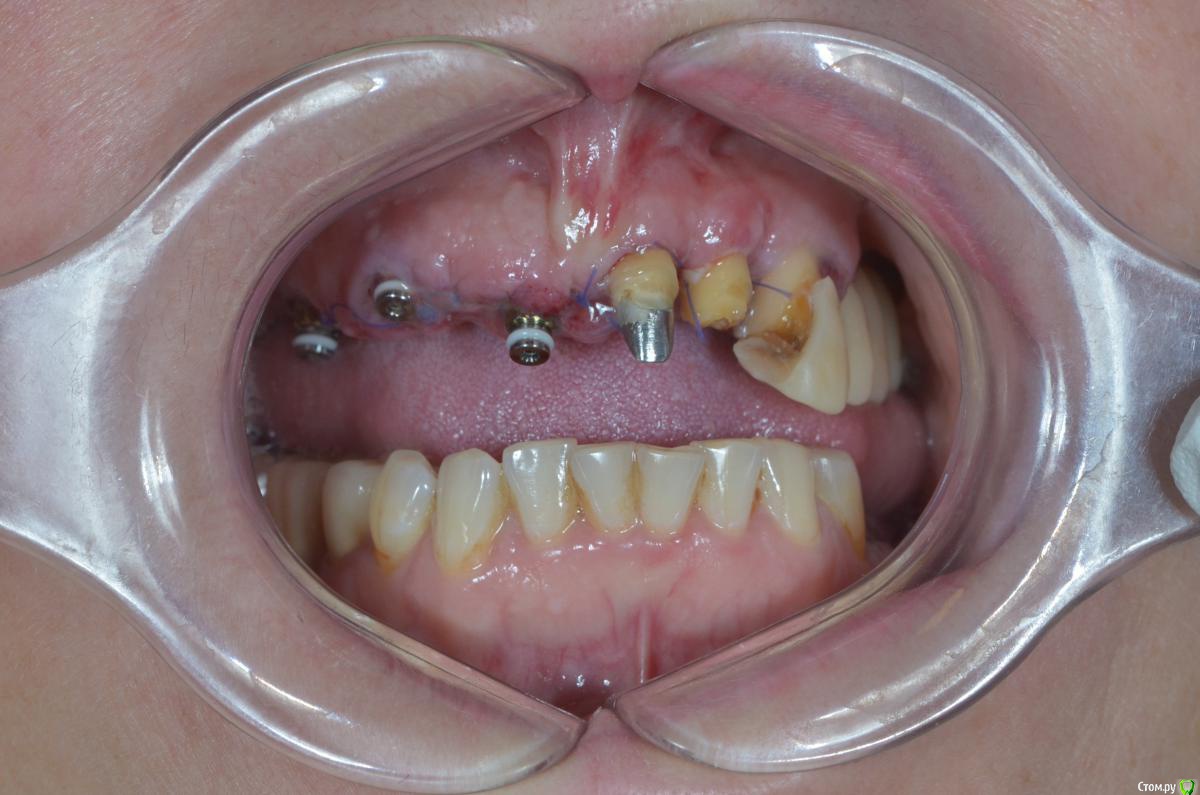

gangsta85 Опубликовано 23 декабря, 2018 Автор Поделиться Опубликовано 23 декабря, 2018 На второй день появился вот такой отек, пока наблюдаем, если станет хуже думаю снять времянки, подкорректировать профиль. Ссылка на комментарий

vadyasti Опубликовано 2 января, 2019 Поделиться Опубликовано 2 января, 2019 (изменено) На второй день появился вот такой отек, пока наблюдаем, если станет хуже думаю снять времянки, подкорректировать профиль.Центральный сосочек зажат!Да и уздечку подрезать было бы не плохо. Изменено 2 января, 2019 пользователем vadyasti Ссылка на комментарий

DoctorT Опубликовано 18 января, 2019 Поделиться Опубликовано 18 января, 2019 На второй день появился вот такой отек, пока наблюдаем, если станет хуже думаю снять времянки, подкорректировать профиль.слишком маленький срок, чтобы судить. Обычно на 3 день максимальный отек. На 10 можно уже делать выводы. Ссылка на комментарий